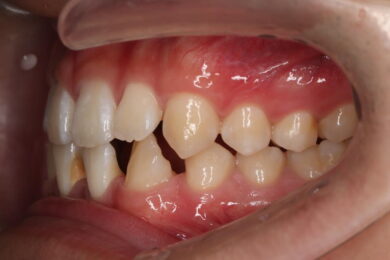

下顎の前歯は通常6本ですが、中央から2番目の歯(側切歯)が左右2本とも欠損している先天性欠如の患者様です。

初診時、下顎だけでなく、上顎の正中(真ん中)にも空隙(隙間)がありました。

• 治療前